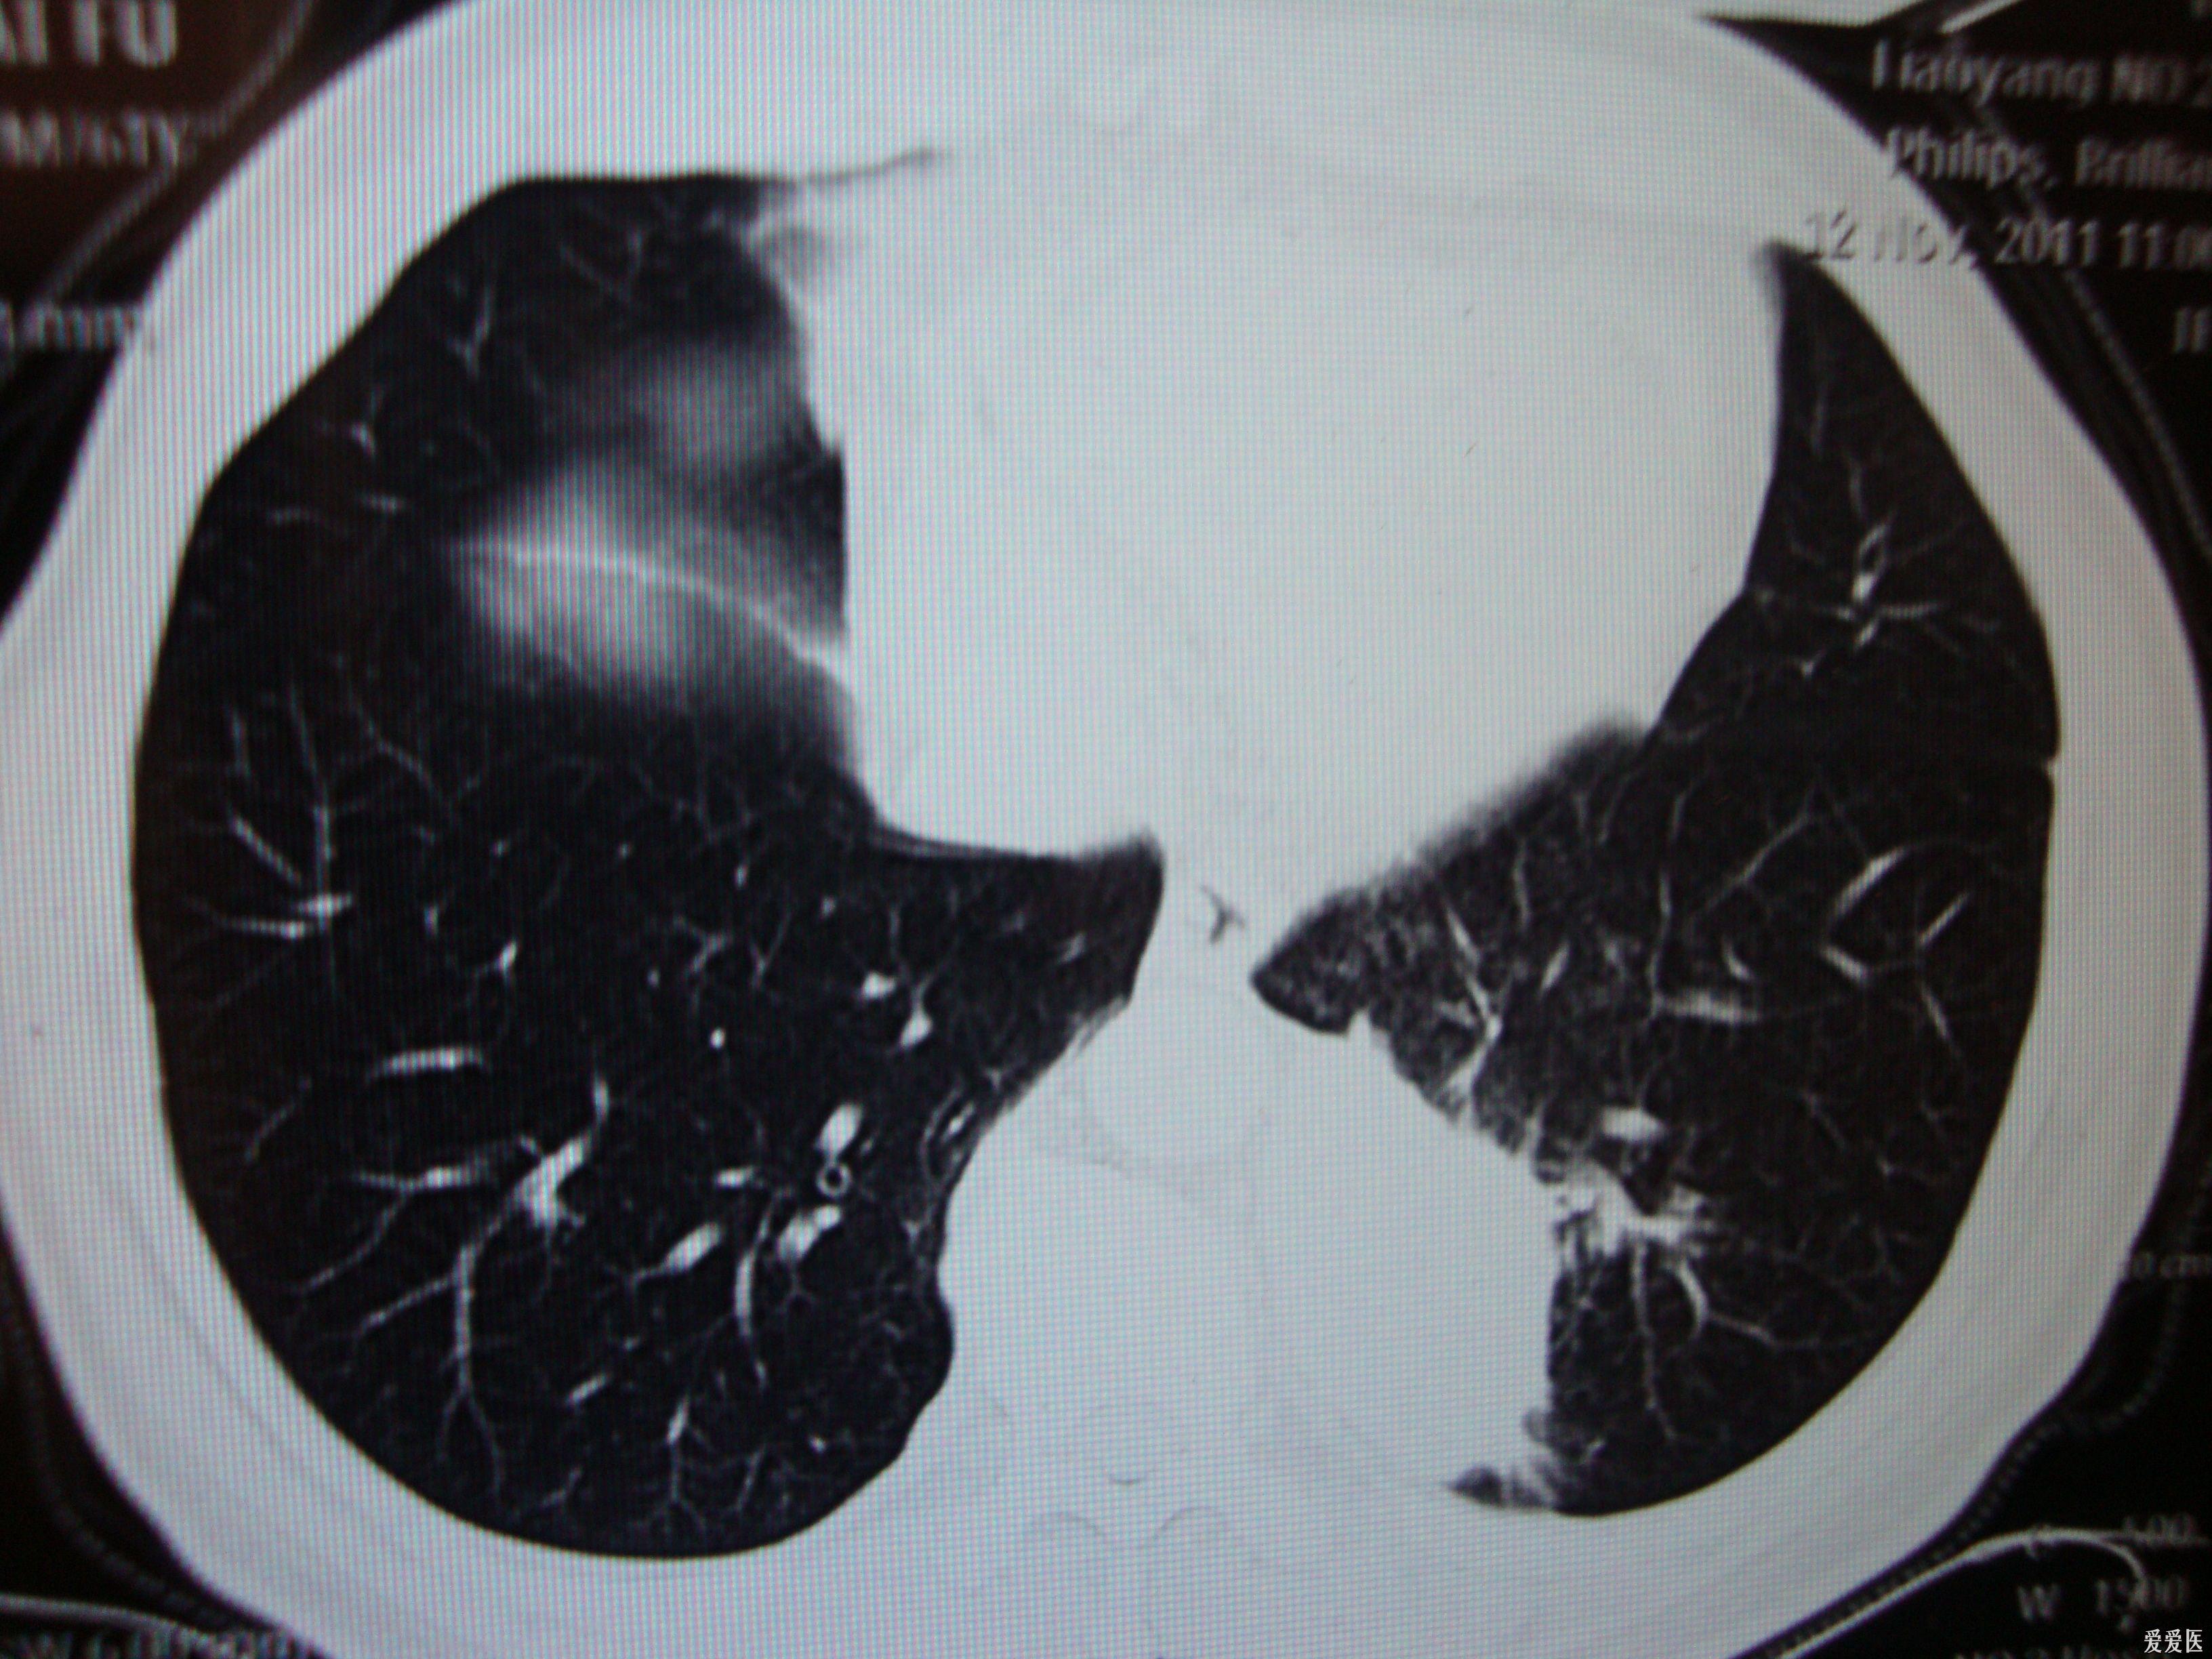

手把手教你ct看气胸,一目了然!

肺部感染ct怎么看看完这篇立刻入门

请各老师给看一看肺ct

69 结果反馈(病例) 69 x13664:左肺上叶占位病灶 ct诊断:左肺上